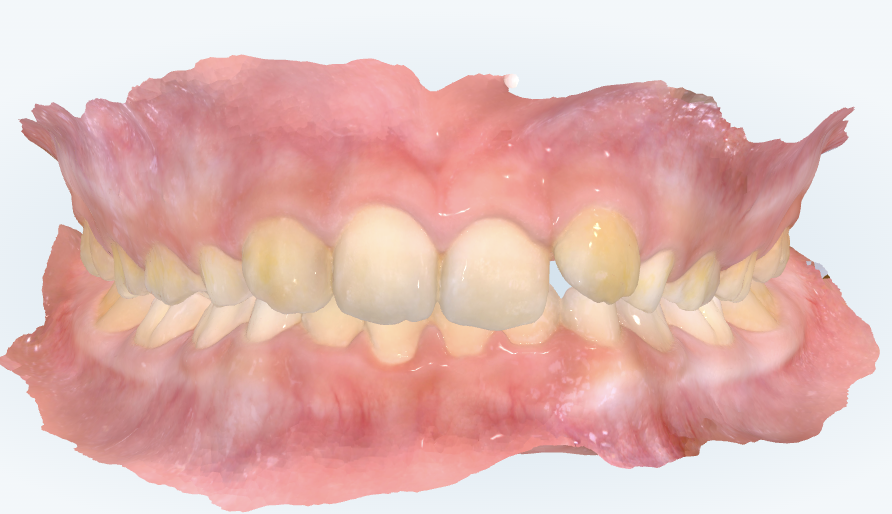

初診時の画像診断

上下の歯並びにガタガタがあります。

前歯の噛み合わせが深いです。